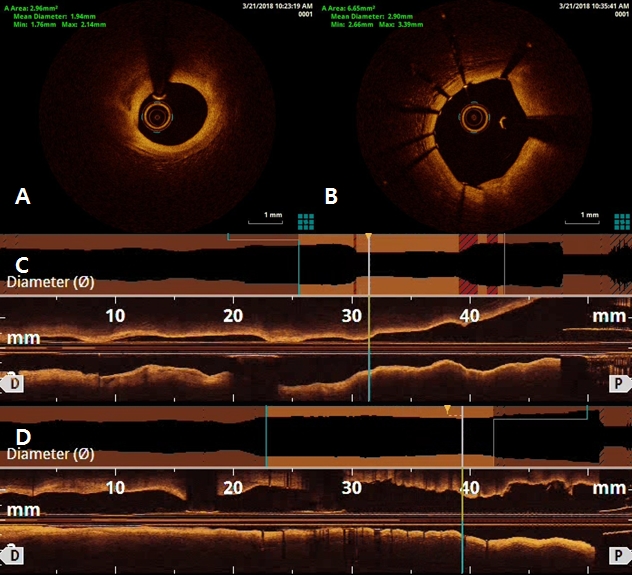

After 3 days later, we performed 2nd stage PCI for proximal LAD. CAG reveled moderate stenosis in proximal LAD (Figure 4A), so we examined optical coherence tomography (OCT) for further evaluation. It showed large amount of plaque (minimal lumen area [MLA] 2.62 mm2) (Figure 5A and 5C). We directly implanted 3.25 and 18 mm everolimus-eluting stent (Xience Alpine®), but follow-up CAG showed mild under-expansion, so we did additional ballooning using 3.25 x 10mm non-complaint balloon (Figure 4B and 4C). Follow-up OCT and CAG showed good distal flow without significant residual stenosis. (post-PCI cross sectional area [CSA] 6.65 mm2) (Figure 4D, 5B and 5D). Because of no-reflow phenomenon for RCA in previous PCI, we performed follow-up CAG and OCT for RCA. CAG and OCT showed stent underexpansion with neointima rupture and large amount of residual thrombi in mid RCA (MLA 2.39 mm2) (Figure 6A, 6B, 7A and 7C). So we did ballooning using 3.25 x 10 mm non-complaint balloon for mid RCA (Figure 6C). Follow-up CAG and OCT showed good distal flow without significant residual stenosis. (CSA 5.03 mm2) (Figure 6D, 7B and 7D). He was discharged without any complications.

Figure 5. Optical coherence tomography (OCT) findings of left anterior descending artery (LAD). OCT showed large amount of plaque in proximal LAD (A and C). There was no significant residual stenosis in proximal LAD after stenting and additional ballooning using non-complaint balloon (B and D)